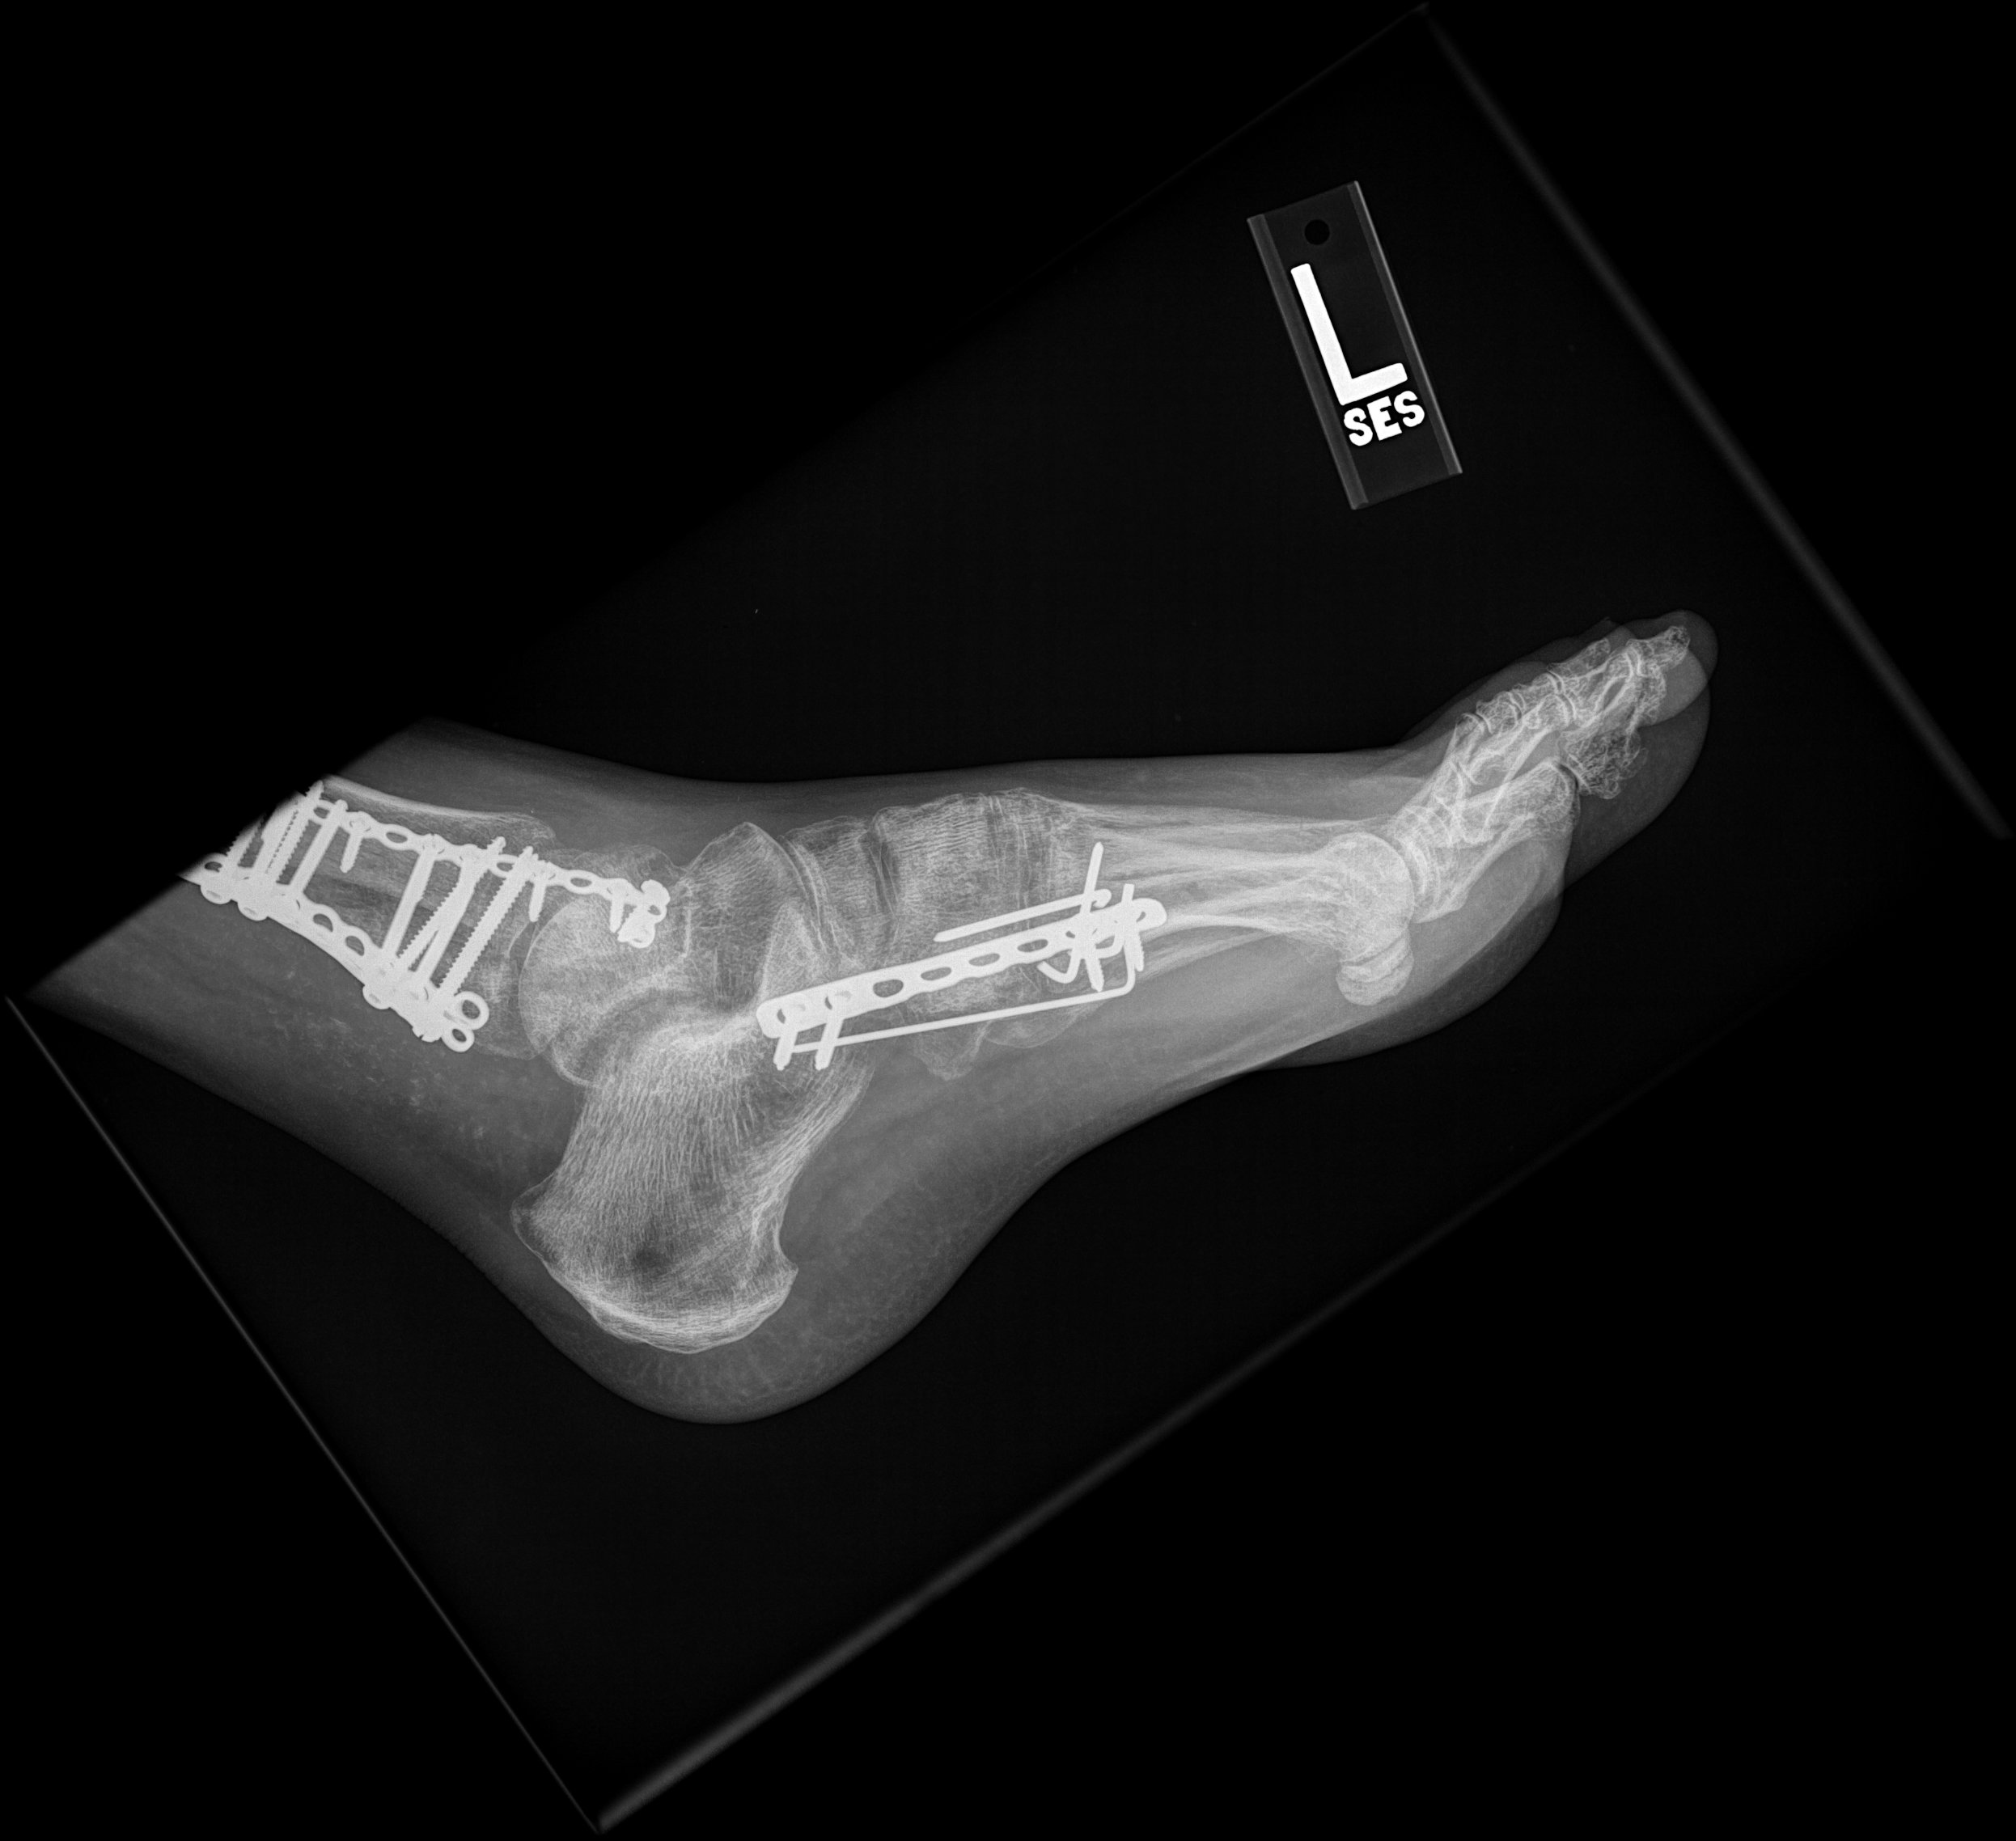

The last X-ray image of my left foot prior to the plate and pins being removed.

My last physical miracle relates to the screws and plates holding my ankle together.  About a week after the accident, my ankle was rebuilt with 3 plates and over 20 screws. I was told following surgery that the screws would never come out. Never. My doctor was emphatic. In fact, my doctor said, “If they come out, your whole ankle will fall apart!” But the left side of my ankle was extremely painful.  For months, I repeatedly requested my doctor to remove the plates and screws on that side.  Six months following the accident, I renewed the request to my doctor.  After reviewing X-rays from that visit, he told me the screws could be removed the following summer.  Only the Lord could produce such thorough healing after such extensive damage.  God enabled my doctor to have incredible skill and an immense amount of wisdom to know exactly how to treat my injury.